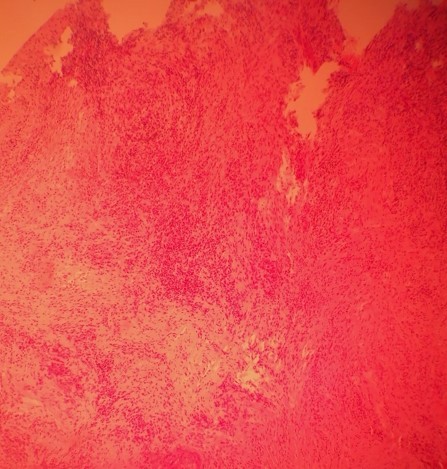

Histopathology revealed complex proliferation of a highly differentiated, stratified, squamous epithelium with keratin-filled crypts resembling rabbit burrows. The mitosis rate of the epithelial cells was normal, and only mild atypia was evident. Inflammatory response in the stroma with an infiltration of lymphocytes and neutrophils was also noted (Figures 3 and 4).

OCC has a distinctive histοlogical appearance, with well-differentiated squamous epithelium that extends deep into the connective tissue with multiple, branching, keratin-filled crypts (described as rabbit burrows), absent or mild cytological atypia (usually limited to the basal and parabasal layers), and normal to little mitoses; inflammatory stromal reaction, mainly consisting of lymphocytes and neutrophils, may be observed, along with discharging abscesses.4,7,9 This patient exhibited most of the histological hallmarks of OCC.